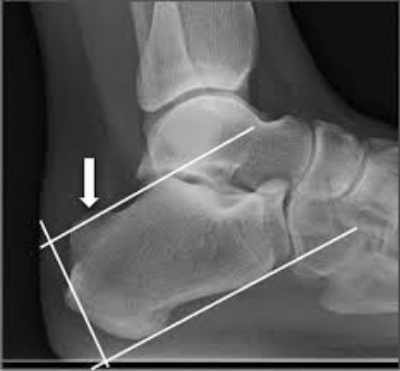

La deformidad de Haglund es el crecimiento excesivo de la parte superior externa de la tuberosidad posterior del calcáneo lo que produce un abultamiento en la parte posterior del talon.

Este tipo de deformidad se asocia con gran frecuencia a pacientes con inversión de la articulación subastragalina y puede provocar la inflamación de las bursas adventicias subcutánea y preaquilea.